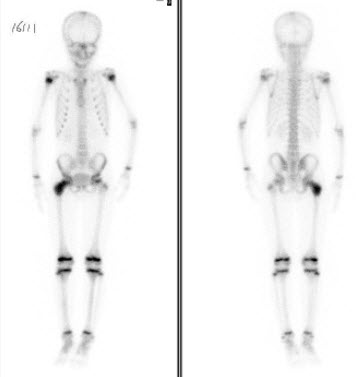

99、多项选择题

患者48岁,右乳癌术后7年,感颈部疼痛2个月,行99Tcm-MDP骨显像如图,可能的诊断是()

A.大致正常的影像

B.下位颈椎有病理性骨折

C.下位颈椎有骨转移

D.双侧股骨远端骨转移瘤

E.骨质疏松征象

100、单项选择题 局部心室壁运动呈反向搏动常提示()